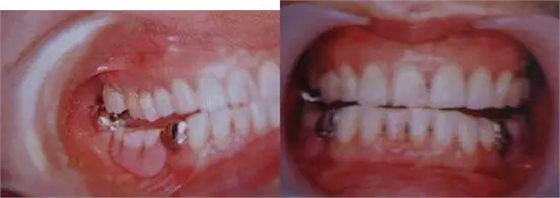

圖9.上頜和下頜第二磨牙中發(fā)生的前方誘導干擾引發(fā)的張口困難。

下頜磨牙的遠中頰側牙尖的近中頰側斜面和上頜磨牙的近中頰側牙尖的遠中腭側斜面相接觸。

圖10.不考慮下頜第三磨牙的咬合平面破壞的修復體制作完成后,后方磨牙干擾引發(fā)的前方誘導干擾。